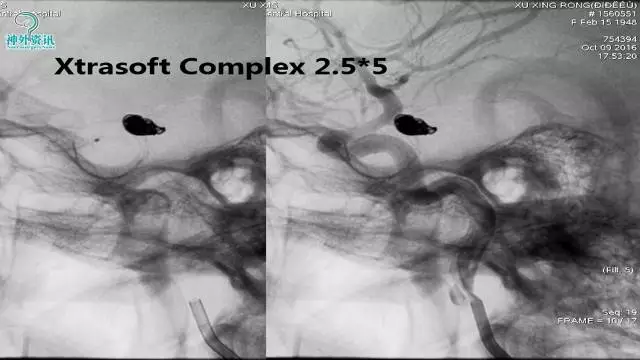

今天为大家分享的是“强生医疗CNV-神经介入专栏”第三十六期,由重庆第三军医大学附属新桥医院神经外科刘俊带来的“Galaxy弹簧圈在不规则动脉瘤中的临床应用”精彩讲课视频及PPT,欢迎观看。文章仅代表作者个人观点,如有不同见解,欢迎同道斧正!